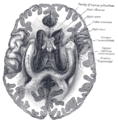

العصب البصري يتألف من محاور عقد عصبية للشبكية وخلايا Portort. وهو يترك المدار (العين) عبر القناة البصرية ،بشكل postero-medially تجاه chiasm البصرية حيث يوجد partial decussation من الألياف من حقول البصرية للأنف من كلتا العينين. معظم المحور العصبية للعصب البصري تنتهي في lateral geniculate nucleus حيث المعلومات تنتقل إلى القشرة البصرية، في حين أن المحاور العصبية الأخرى تنتهي في الـ pretectal nucleus وتشارك في حركات العين الانعكاسية ومحاور عصبية أخرى تنتهي في suprachiasmatic nucleus وتتدخل في تنظيم دورة النوم واليقظة. ويزيد قطرها حوالي 1.6 ملم من داخل العين، إلى 3.5 ملم في المدار إلى 4.5 ملم داخل فضاء الجمجمة. وأطوال مكونات العصب البصري 24 ملم في المدار، 9 ملم في القناة البصرية و 16 مم في فضاء الجمجمة قبل أن ينضم إلى chiasm البصرية. هناك ،يحدث الـ decussation الجزئي وحوالي 53 ٪ من الألياف تتشابك لتكون الـ optic tracts. معظم هذه الألياف تنتهي في جسم geniculate الأفقي.[2]